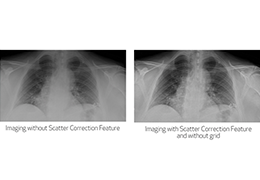

Window/level (brightness and contrast) presets.